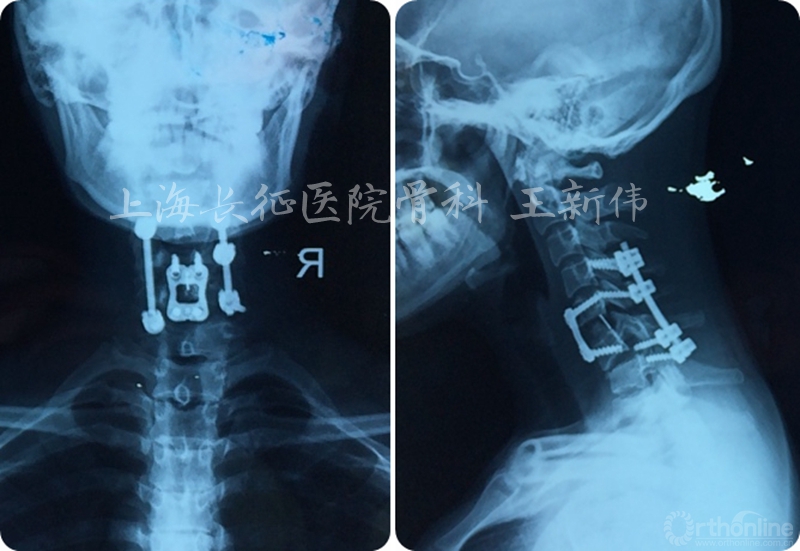

第一次术前颈椎CT三维重建

第一次术后颈椎CT三维重建,可见C6/7双侧仍存在关节绞锁